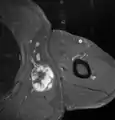

Fig. 1 Micrograph of bone formation in a liposarcoma tumor

Fig. 2 Micrograph of a dedifferentiated liposarcoma tumor

Dedifferentiated lipoosarcomas (DDL) occur most frequently in middle-aged and older adults with a peak incidence in their sixth to eighth decades.[8] Rarely, these tumors have developed in children and adolescents.[5] DDL tumors most commonly occur in the retroperitoneal space but, similar to ALT/WDL, may occur in the extremities, paratesticular area, mediastinum, head, or neck.[8] Less than 1% of all DDLs develop in superficial soft tissues[8] or the eye socket.[21] At presentation, DDL tumors typically are painless, large, may have been slowly and progressively enlarging for years,[8] and on routine X-rays contain areas of calcium deposition (exemplified by Fig. 1 in the Histopathology of liposarcomas section).[22][23] Less commonly, affected individuals have signs and/or symptoms due to their tumor's impingement on an organ (e.g. abdominal pain caused by blockage of the intestines or urinary tract obstruction caused by blockage of the urethra). Very rarely, individuals with DDL present with one or more signs or symptoms of chronic inflammation (see B symptoms) and/or one of the endrocrine, neurological, mucocutaneous, hematological, or other tissue-related paraneoplastic syndromes. The signs and symptoms of chronic inflammation and the various paraneoplastic syndromes are caused by the tumors' secretion of cytokines, hormones, prostaglandins, and/or other systemically acting agents; they completely disappear after the DDL is successfully treated.[8]

The histopathological appearance of DDL tumors (see Fig. 2 in the below Histopathology of liposarcomas section) varies widely but most frequently exhibits features of undifferentiated pleomorphic sarcomas (which are tumors densely populated with variably sized and shaped cells containing variability sized and shaped nuclei) or spindle cell sarcomas (which are tumors consisting of spindle-shaped cells in a connective tissue background). Different parts of DDL tumors often show variations in the appearances of their background connective tissues: these tissues may be myxoid (i.e. consisting of a clear, mucus-like substance which when stained using a standard H&E stain method appears more blue or purple than the red color of normal tissues) or myxocollagenous (i.e. high collagen fiber content in a myxoid background), and, in ~5% of cases, have areas of osteoid (see Fig. 1 in the below Histopathology of liposarcomas section) or cartilaginous material. The tumors also show large variations in their cell contents. For example, up to 10% of DDL tumors have areas with ALT/WDL histopathology [8] and rare cases of DDL have areas containing meningothelial-like whorls of flat cells.[24][25]